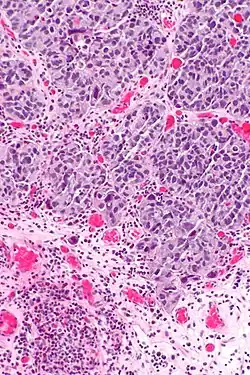

Inwazja warstwy mięśniowej raka urotelialnego

Inwazyjny (naciekający) rak urotelialny jest definiowany jako obecność inwazji nowotworowej poniżej błony podstawnej urotelium[74]. Makroskopowo inwazyjne nowotwory urotelialne mogą przyjmować formę brodawkowatą, polipowatą, guzkową, litą, tworzyć rozlany naciek ściany pęcherza moczowego. Zmiany mogą występować pojedynczo lub wieloogniskowo[75]. Typowo większość guzów pT1 jest brodawczakowata o niskim lub wysokim stopniu złośliwości histologicznej, z kolei guzy o większym zaawansowaniu pT2–T4 wykazują morfologię niebrodawczakowatą i cechują się wysokim stopniem złośliwości[76][77].

Mikroskopowo w utkaniu obecne są komórki tworzące gniazda, sznury komórek lub pojedyncze komórki pooddzielane desmoplastycznym podścieliskiem[76][78]. Możliwy jest bardziej rozlany wzór wzrostu nowotworu, w którym komórki tworzą arkusze, przy czym również w takim utkaniu spotyka się ogniskowo występujące gniazda komórek[78]. Komórki cechują się umiarkowaną do obfitej ilością amfofilnej lub eozynofilnej cytoplazmy i dużym hiperchromatycznym jądrem komórkowym. Jądra komórkowe wykazują znaczną pleomorficzność, nieregularne, kanciaste granice. Liczba i wygląd jąderek wykazuje znaczną zmienność. Gniazda komórek nowotworowych zwykle indukują reakcję desmoplastyczną podścieliska. Obecne są liczne figury mitotyczne i możliwa jest obecność nieprawidłowych figur mitotycznych. W podścielisku większości guzów jest obecny naciek limfocytów i komórek plazmatycznych, naciek najczęściej jest wyrażony ogniskowo od łagodnego do umiarkowanego stopnia, ale może być nasilony i rozlany[76][78]. Może być widoczna inwazja naczyń[78].

Kluczowym elementem wpływającym na rokowanie jest głębokość nacieku nowotworowego. Początkowo inwazja blaszki mięśniowej właściwej może przebiegać jako obecność pojedynczych komórek, klastry lub gniazda komórek w górnych warstwach blaszki mięśniowej właściwej, zwykle skojarzonej z infiltracją komórek zapalnych[79]. W późniejszych etapach inwazji obecne są klastry lub rozlane arkusze komórek nowotworowych w obrębie blaszki mięśniowej właściwej[79].